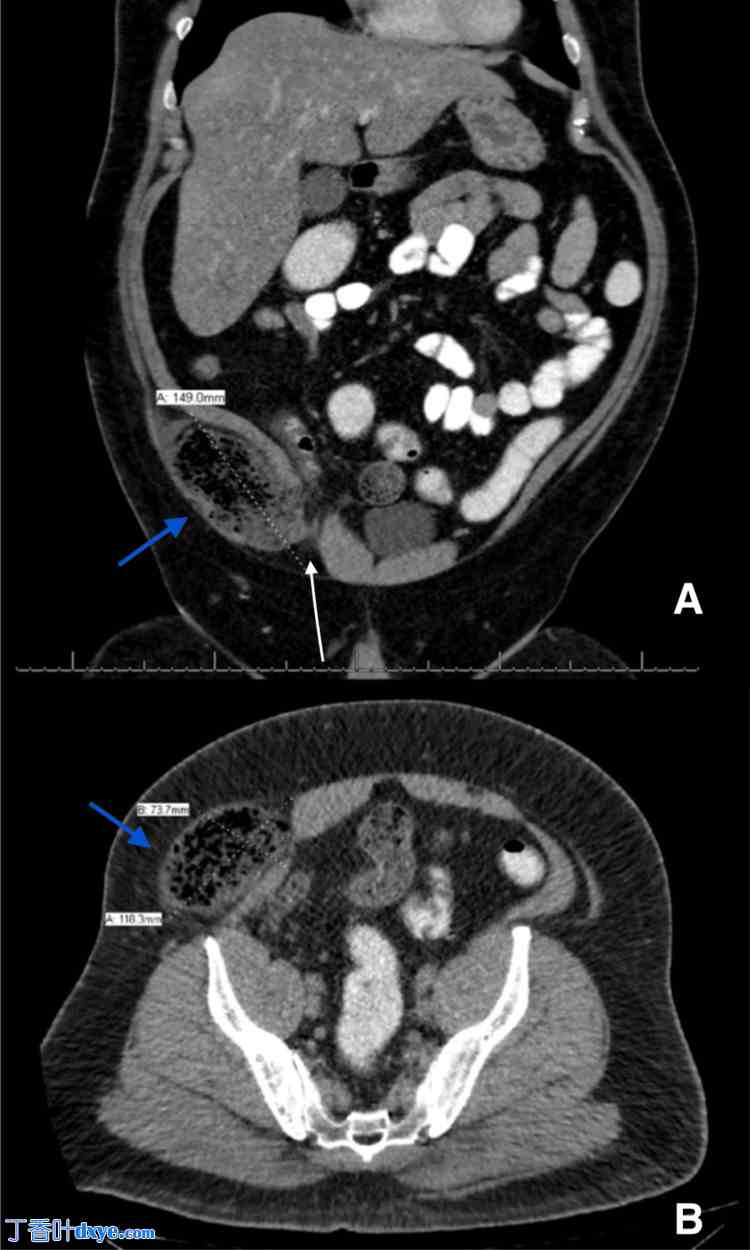

On physical examination, he was afebrile, and his BMI was 46 kg/m2. The abdomen was soft and lax, with tenderness and rebound tenderness on the right iliac fossa, which raised the suspicion of acute appendicitis given his clinical presentation. On investigation, the complete blood count was unremarkable. A CT scan of the abdomen performed with intravenous, oral, and rectal contrast showed a right lower abdominal wall hernia sized 11.8 x 7.3 x 14.9 cm, seen lateral to the right rectus muscle. Inferiorly, it was close to the inguinal canal with superior extension at the level of the iliac crest, containing parts of the terminal ileum, the ileocecal valve, and the base of the cecum (Figure 1).

Figure 1. CT of the abdomen.

A: Coronal cut of the abdominal CT scan showing the incarcerated wall of the cecum, ileum, and appendix (blue arrow points to the herniated bowel) in relation to the inguinal region(white arrow points to the abdominal wall defect); B: Axial cut with similar findings